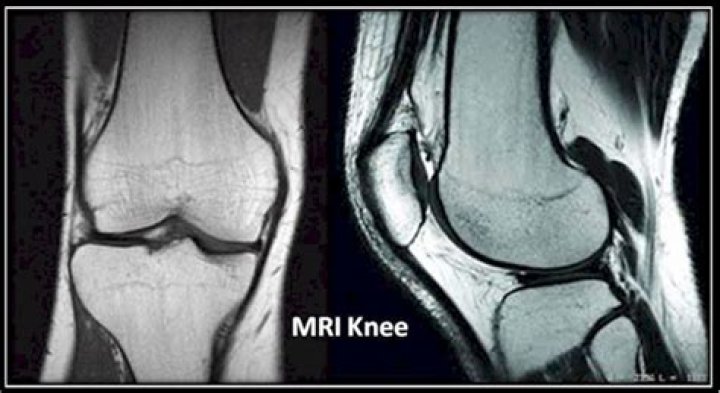

Knee MRI. Magnetic resonance imaging (MRI) of the knee uses a powerful magnetic field, radio waves and a computer to produce detailed pictures of the structures within the knee joint. It is typically used to help diagnose or evaluate pain, weakness, swelling or bleeding in and around the joint.

MRI gives a good picture of the size of a meniscus tear and where it is. It also shows ligaments, cartilage, and tendons. MRIs of the knee are helpful to identify a meniscus tear and to find any related injuries to the ligament, cartilage, and tendons.

Will an MRI show arthritis in the knee?

MRI is the most effective way to diagnose problems within any joint and the image sensitivity makes it the most accurate imaging tool available in detecting arthritis and other inflammatory changes.